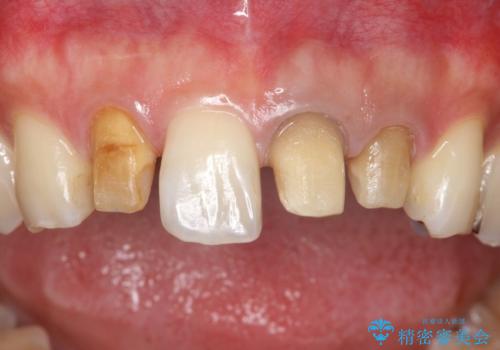

- 全体的なガタガタと前歯をきれいにしたいとのことで来院されました。

下の歯は重度のガタガタがあり、上の前歯は何本かが神経の治療がしてある状態でした。

インビザラインにて歯並びを整え、上顎の前歯にセラミックを装着する計画としました。